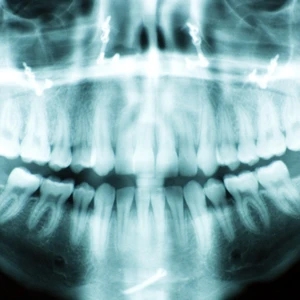

Digital X Rays

Traditionally, dentists use x-rays to find out what's going on below the surface, developing them in a darkroom full of chemicals, and examining the resulting films on a special light board.

Digital radiography entirely outmodes that cumbersome process. Now, a tiny sensor placed in the mouth acts like a miniature VCR camera with an x-ray sensitive chip, exposing you to 50%-90% less radiation exposure than with traditional x-ray techniques. The resulting highly detailed image of your mouth is almost instantaneously translated onto our computer screen, carrying with it all the conveniences of other digitized images. We can rotate it, magnify it, adjust it for contrast, and even color-code it for educational purposes. Because it helps our patients clearly understand the root issues behind their dental health, we're able to work together to determine the very best treatment options for each case.